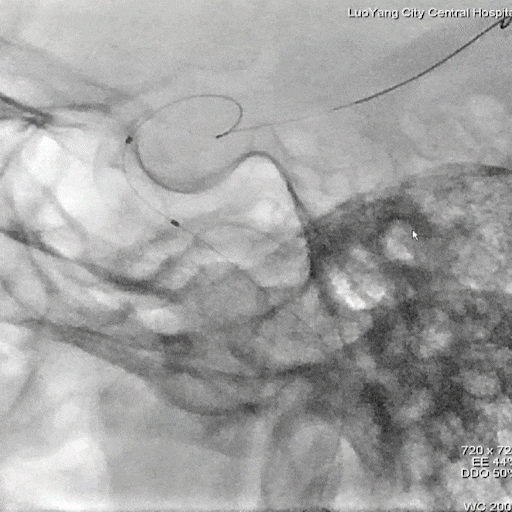

主动脉弓上血管多发斑块形成。

左侧锁骨下动脉显示左侧椎动脉开口重度狭窄,狭窄率85%,供血至PICA。

双侧颈动脉造影提示双侧颈内动脉多发斑块形成,远端血管显影良好。

右侧锁骨下动脉造影提示右侧椎动脉主供血,开口无狭窄,椎动脉V4段局限性重度狭窄,狭窄率 80%,远端基底动脉及分支血管显影良好。

正侧位造影提示右侧椎动脉重度狭窄。

造影证实狭窄较前明显改善。

术后造影造影证实支架打开良好,贴壁良好,无残余狭窄,远端未见明显栓塞表现。